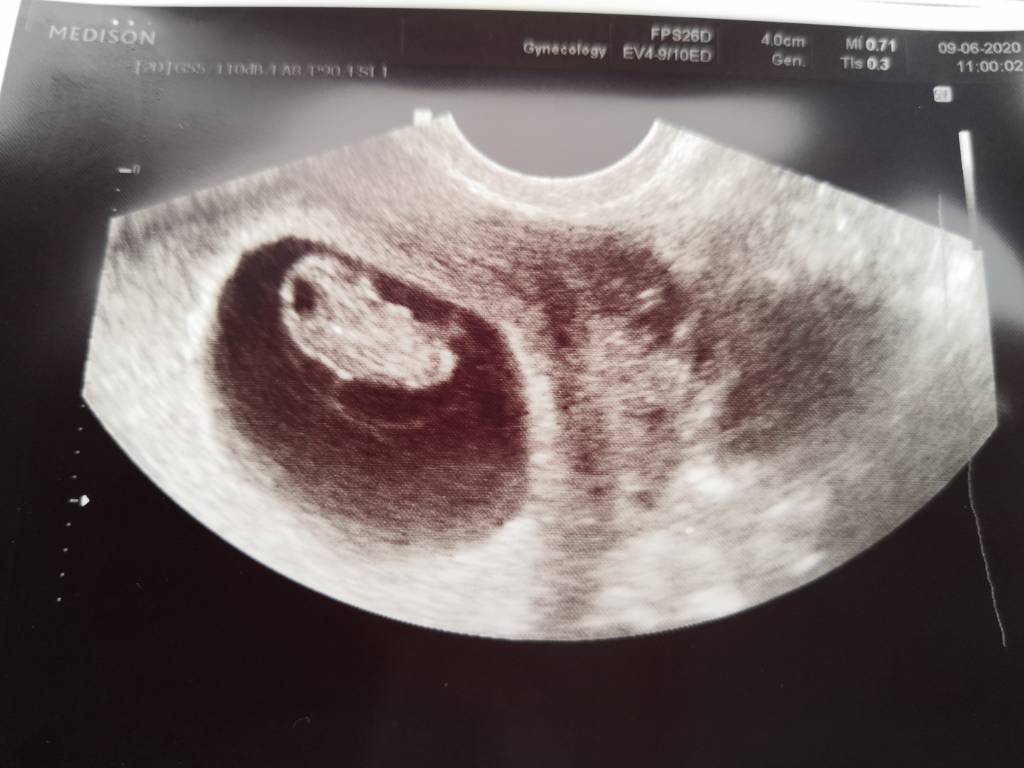

Ja po wizycie już dosyć dawno, wszystko jest dobrze :) maluszek ma 1,64cm to 8tc+0 czyli idzie mi idealnie z miesiączka 😁 akcja serduszka koło 160 :) ależ jestem szczęśliwa, nie macie pojęcia 🥰 od razu po wizycie położna pobrał mi krew do badań i karta ciąży założona ❤️

Ja po wizycie już dosyć dawno, wszystko jest dobrze :) maluszek ma 1,64cm to 8tc+0 czyli idzie mi idealnie z miesiączka 😁 akcja serduszka koło 160 :) dodaje też zdjęcia ❤️ ależ jestem szczęśliwa, nie macie pojęcia 🥰 od razu po wizycie położna pobrał mi krew do badań i karta ciąży założona ❤️

No, wiedziałam że dziewczyny pomogą [emoji3059] zerknij jaka u mnie była różnica pomiędzy 6t6d a 8t3d [emoji116]

No, wiedziałam że dziewczyny pomogą [emoji3059] zerknij jaka u mnie była różnica pomiędzy 6t6d a 8t3d [emoji116]Zobacz załącznik 1133982Zobacz załącznik 1133983